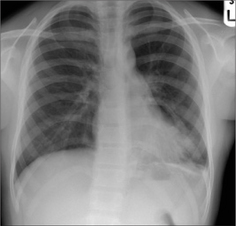

image Mucus plugging may cause a lobe to collapse.

image

Figure 29.2 Acute asthma. Unexplained clinical deterioration. Collapse of the left lower lobe due to a mucus plug in the bronchus.